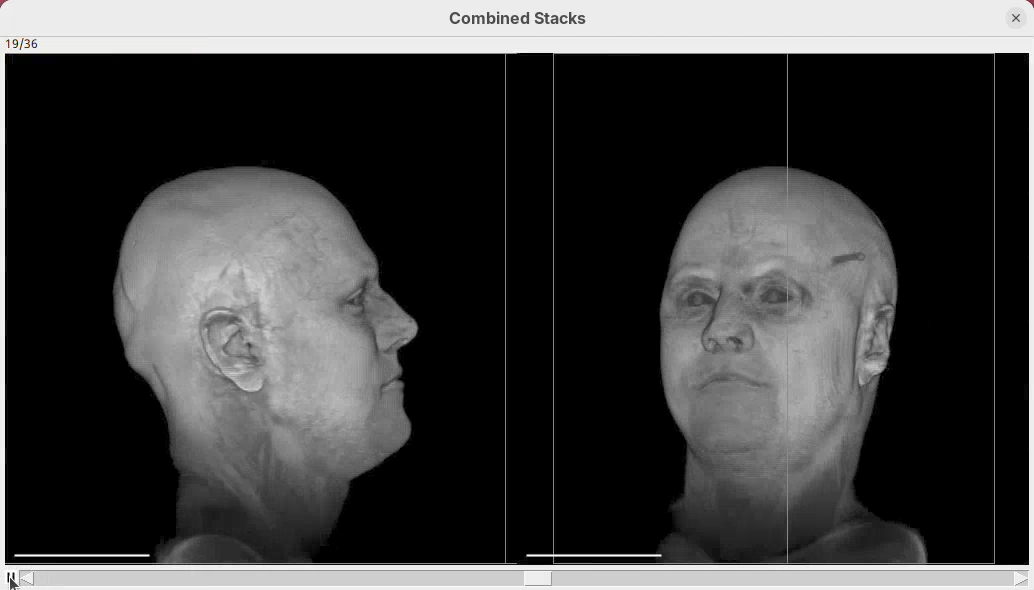

- zoom by a factor of 2Tweak appearance

We can now also tweak the animation to reach the final appearance that we want. For example, we can change scale bar width and height and hide the bounding box lines around the sample.

- Write the code below in the editor and press

Run:

At frame 0:

- rotate by 90 degrees around (0, 1, 0)

- change channel 1 bounding box z to (0, 129)

- change bounding box visibility to off

- change scalebar length to 50

- change scalebar width to 10

- change scalebar offset to 20

From frame 0 to frame 71:

- rotate by 180 degrees horizontally

- change channel 1 bounding box max z to 60

- zoom by a factor of 2

From frame 72 to frame 100:

- change channel 1 bounding box max z to 129

- zoom by a factor of 0.5Note how there’s no longer a bounding box and the scale bar is much more visible.